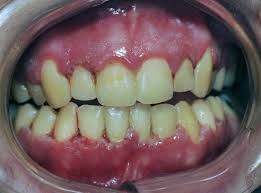

Trench mouth is most common in teenagers and younger adults. This study was designed to investigate the extent of probing attachment loss detectable followin. Patients with this condition also suffer from fever and halitosisi. Localized or generalized periodontitis with rapid sudden onset with excruciating intense pain. Necrotizing ulcerative gingivitis nuii can occur in a mouth essentially free of any other gingival involvement or he superimposed on underlying chronic gingival disease.

It has an acute clinical presentation with the distinctive characteristics of rapid onset of interdental gingival necrosis gingival pain bleeding and halitosis. Acute necrotizing ulcerative gingivitis anug occurs most frequently in smokers and debilitated patients who are under stress. Treatment of acute necrotizing ulcerative gingivitis. Acute necrotizing ulcerative gingivitis anug has been generally considered as a gingivitis. Acute necrotizing ulcerative gingivitis definition acute necrotizing ulcerative gingivitis or anug is characterized as a plymicrobial infection of the patient s gums that normally leads to bleeding inflammation necrotic gum tissue and deep ulcerations.

Dental tape rather than floss. However clinical impressions suggest that periodontal attachment loss is one of the sequelae of the disease. Necrotizing ulcerative gingivitis is described as the initial stage of the condition. Diagnosis is based on clinical findings. Necrotizing ulcerative gingivitis can usually be overcome in a couple of weeks with professional dental assistance commitment to brushing flossing and rinsing regularly and minimization of risk factors.